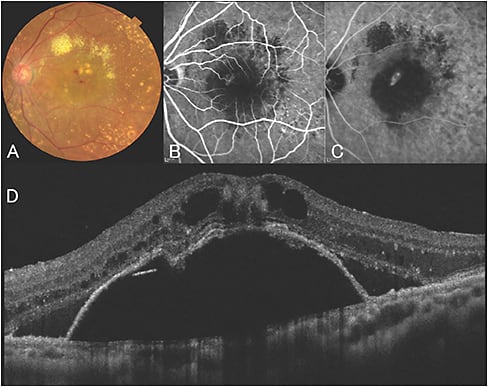

RAP (Figure 2) is a different entity of exudative AMD that was first reported by Yannuzzi and associates in 2001.38 This subtype is characterized by neovascularization originating from the retinal capillaries and not from the choroid, as in the other phenotypes of exudative AMD.

Figure 2. Typical case of retinal angiomatous proliferation (RAP, stage 3). A) Color fundus photography. B) Fluoroscein angiograph image, early phase. Retinal-retinal anastomosis is visible. C) ICG angiography image, late phase. Hyperfluorescent lesion called “hot spot” is apparent. D) OCT image of vertical section. Cystoid macular edema and retinal pigment epithelial detachment (PED) imply the retinochoroidal anastomosis.

Freund et al called the neovascularization of the RAP lesion “type 3 neovascularization,” distinguishing it from type 1 or 2 neovascularization originating from a choroidal vessel.39 RAP has a pathognomonic profile, including an older age, a higher ratio of women, a high tendency for bilateral affection, and an accumulation of soft drusen or reticular pseudodrusen at the macula.40

RAP lesions are categorized into three stages.38 Stage 1 RAP is intraretinal neovascularization (IRN) that originates from the deep retinal plexus. Stage 2 RAP is determined by the extension of IRN into the subretinal space, with or without PED. Stage 3 RAP has IRN and CNV connecting via retinochoroidal anastomosis.

The definitive diagnosis of RAP is based on fundus examination, OCT, and angiographic findings. Upon fundus examination, the characteristics of a florid intraretinal hemorrhage, angiectasia of the retinal capillaries, CME, and the accumulation of soft drusen in the macula are notable. With OCT, CME, serous retinal detachment and PED (in cases of stage 2 or 3) are detected.

With fluorescein angiography, retinal-retinal anastomosis in the early phase is valuable in the diagnosis. ICG visualizes the characteristic intense hyperfluorescence called a “hot spot,” corresponding to IRN.38